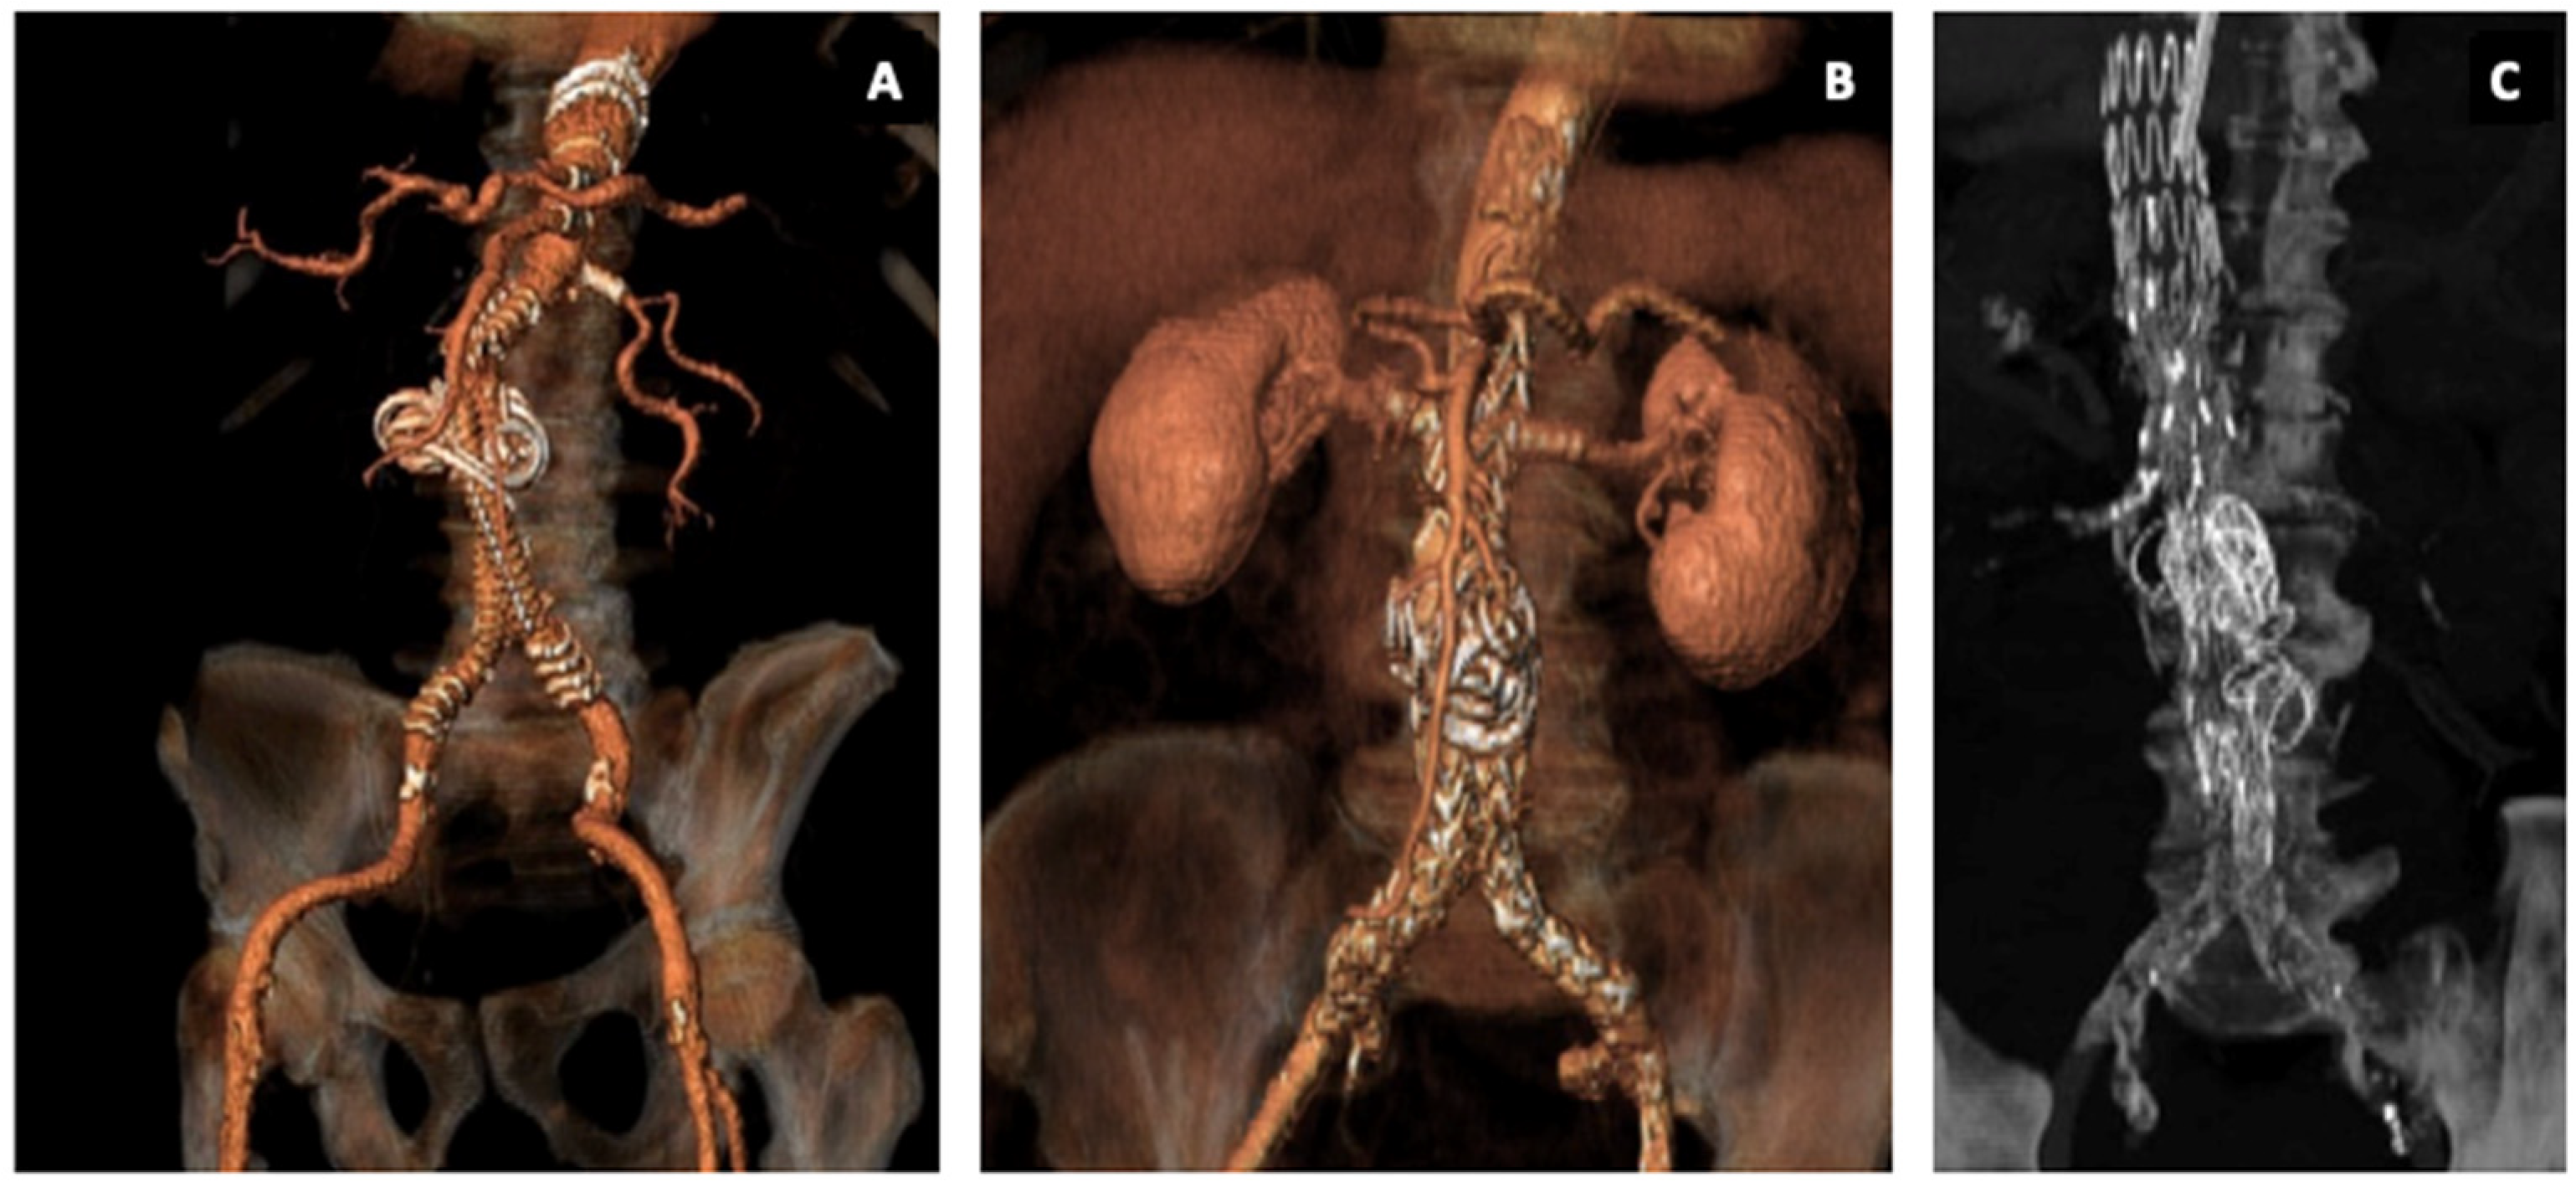

Embo F/BEVAR Case Descriptions and Preliminary Results